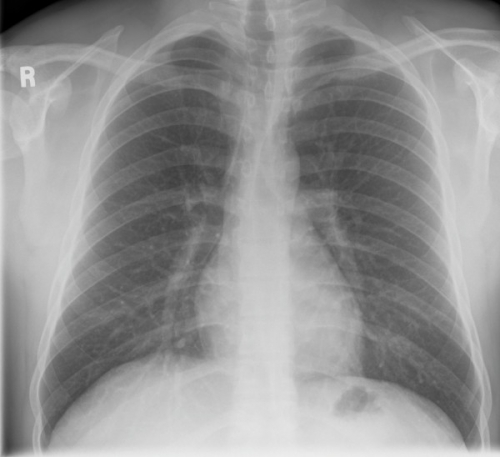

Tool to train medical student's eyes as to what a normal chest x-ray looks like, with over 500 consecutive normal images.